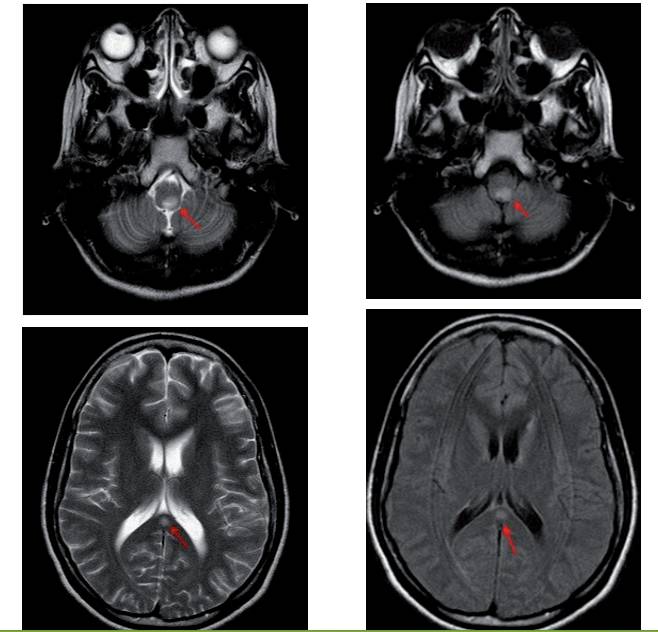

视神经脊髓炎病灶在Tl上常为等或稍低信号,T2及常表现为高信号。特征性病灶位于下丘脑、丘脑、三脑室、导水管、桥脑被盖及四脑室周围。神经脊髓磁共振成像通常显示多个脊髓节段受累,急性期常见脊髓肿胀和明显实质性、环形或线性强化;相对严重的病例可出现髓内多个节段的空腔样坏死灶,更为严重者颈髓病变累及低位延髓,疾病晚期可出现脊髓萎缩。

T2及FLAIR序列延髓背侧和胼胝体压部病变区高信号